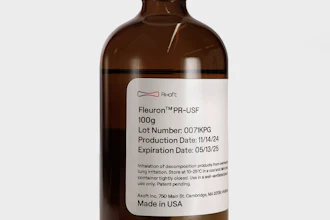

- Environmental Durability: Implantable sensors must be durable enough to withstand the body's constant physiological changes. It was imperative to ensure the sensor's housing was resistant to bodily fluids, temperature fluctuations, and potential chemical interactions in the eye. The materials used were carefully selected to prevent any adverse reactions, in line with ISO 10993 biocompatibility standards. The external housing of the sensor is crafted from biocompatible materials such as titanium and medical-grade polymers, which offer corrosion- and degradation-resistance within the aqueous environment of the eye.